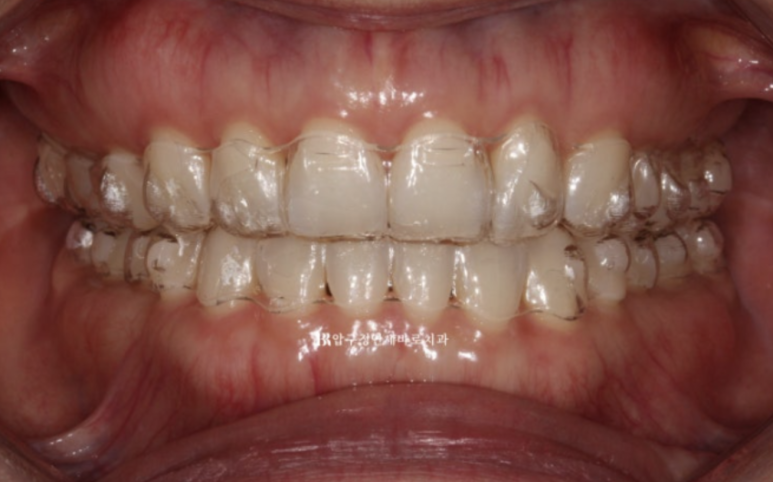

4개월 간 추가장치를 더 껴서 디테일한 부분과 미세공간을 마무리 하여 24년 5월 치료가 마무리 되었습니다.

24.5

Q 인비절라인으로 교합이 제대로 맞지 않는다는 말이 사실인가요?

A. 이는 일부 오해입니다. 정확한 진단과 치료 계획, 그리고 필요 시 보조 장치 활용이 이루어진다면 인비절라인으로도 기능적으로 안정적인 교합을 충분히 만들 수 있습니다. 본 사례처럼 어금니 교합까지 안정적으로 마무리되는 결과도 많습니다.

가위교합이였던 우측 상악 제 2대구치 교합도 잘 유지가 되고 있습니다.

23.07~24.05

악궁 모양과 배열이 잘 잡혔고 재제작때 미니스크류 뺀 자리는 잘 안물어서 흔적이 없습니다.

흉터가 작게 남는 경우도 있지만 흉터도 남지 않는 경우가 많습니다.